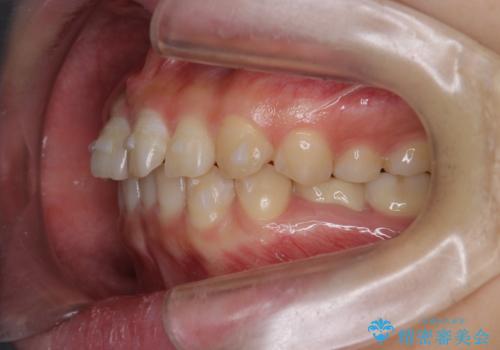

左下に乳歯が残っていましたが、被せ物に穴が空いている状態でした。

乳歯は抜かずに保存的な治療を行いました。

上下の正中が1本分ずれていましたが、ちょうど1本分で目立たず、また、右下の歯が生まれつき少ないことを利用して、最小限の歯の移動にとどめました。

乳歯はまだぐらついたりしていない状態だったため、しっかり虫歯を取り、根の治療も行いました。